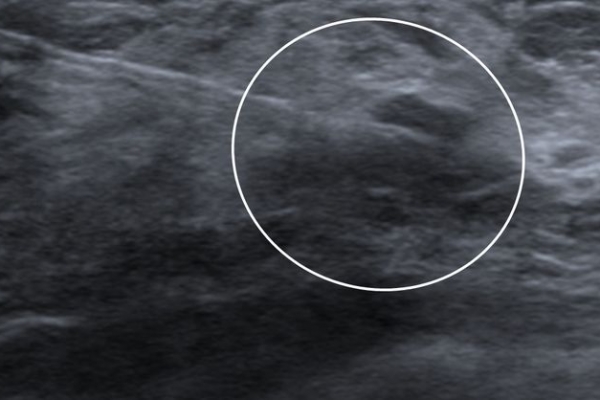

Σε περίπτωση που απαιτείται η χειρουργική αφαίρεση ενός ευρήματος που δε ψηλαφάται από το χειρουργό, τότε γίνεται η τοποθέτηση αγκίστρου σήμανσης (hook) λίγο πριν το χειρουργείο. Το άγκιστρο έχει σκοπό να καθοδηγήσει το χειρουργό για την αφαίρεση του σωστού τμήματος του μαστού, ώστε να αφαιρεθεί με ασφάλεια η ύποπτη βλάβη χωρίς να επηρεασθεί η αισθητική εικόνα του μαστού, πράγμα πολύ σπουδαίο ειδικά σε νέες γυναίκες και σε γυναίκες με μικρό μαστό.